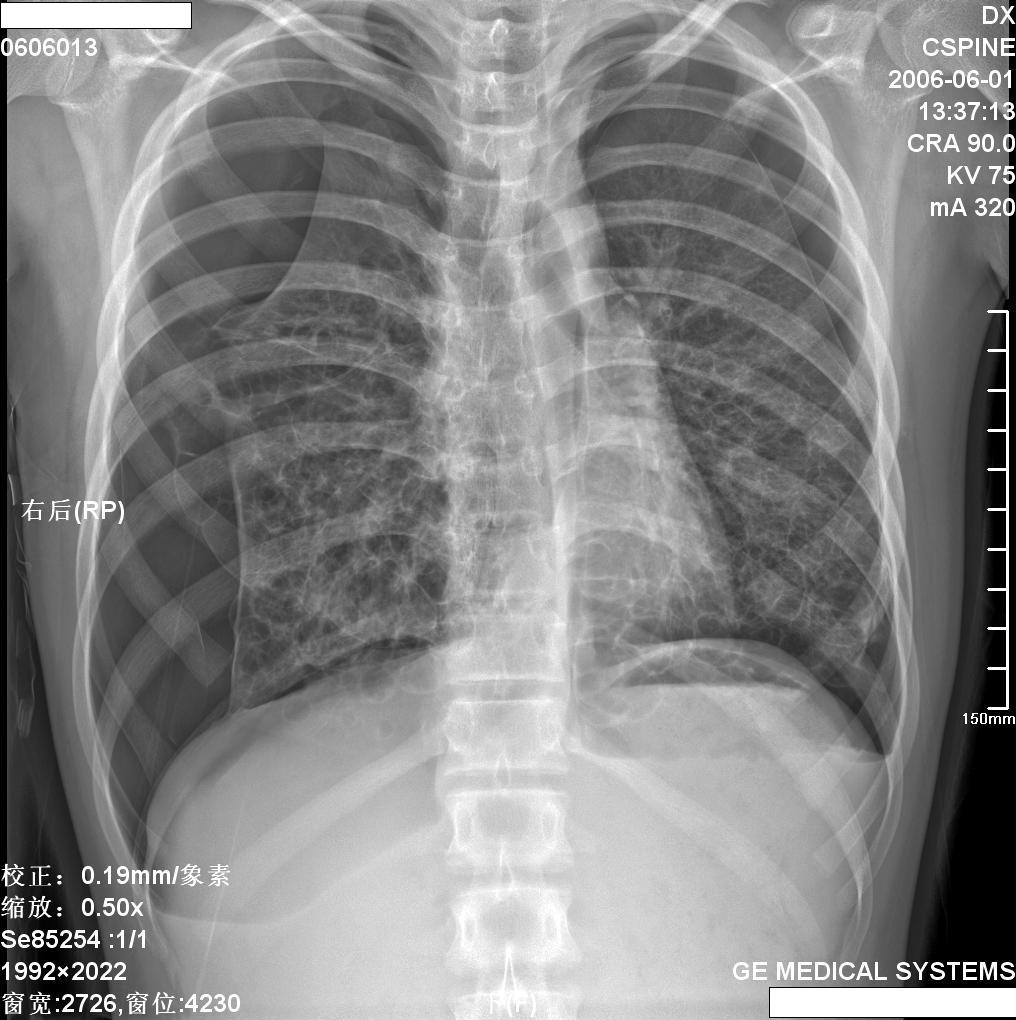

x:双肺中下野多发囊状卷发状影,壁模糊,无液平,双肺纹理强,-------印象:先天支扩并感染.

双肺纹理粗乱,双下肺见网囊小点结影,膈肌低位,颈部见皮下气肿征,侧位可疑纵隔气肿。男性,16岁,无相关病史可考虑1间质性肺炎。2慢支炎或支气管哮喘。3支扩及其他待排请提供病史

王某某,男,16岁,既往无经常咳嗽、咳痰、胸闷、发热史,活动与同龄儿童相似,三月前突感胸、颈前痛、无喘憋,查体胸骨上皮下气肿,双肺呼吸音对称。胸部dr及ct示纵隔气肿,双肺囊肿。近两月反复出现胸痛、喘憋,无发热、黄痰及痰血,呼吸音减低,胸部dr示双侧自发性(张力性)气胸,胸腔闭式引流治愈。频繁发作,左侧引流两次,右侧引流三次。

1.诊断考虑先天性肺囊肿(囊性肺),自发性、张力性气胸,鉴别支气管扩张,先天性囊性腺瘤样畸形等

从上述x线片、ct片看,先考虑先天性肺囊肿(囊性肺),伴气胸、纵隔积气、皮下积气;先天性囊性腺瘤样畸形,一般中叶很少累及.

先考虑先天性肺囊肿(囊性肺),伴气胸、纵隔积气、皮下积气,胸水.先天性囊性腺瘤样畸形